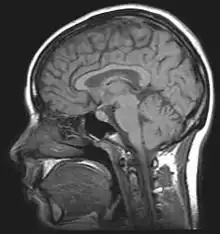

| For the diagnosis, brain scans (such as MRI) should be done to rule out other potential causes. | |

Neuroimaging, usually with computed tomography (CT/CAT) or magnetic resonance imaging (MRI), is used to exclude any mass lesions. In IIH these scans typically appear to be normal, although small or slit-like ventricles, dilatation and buckling[18] of the optic nerve sheaths and "empty sella sign" (flattening of the pituitary gland due to increased pressure) and enlargement of Meckel's caves may be seen.

An MR venogram is also performed in most cases to exclude the possibility of venous sinus stenosis/obstruction or cerebral venous sinus thrombosis.[5][7][8] A contrast-enhanced MRV (ATECO) scan has a high detection rate for abnormal transverse sinus stenoses.[15] These stenoses can be more adequately identified and assessed with catheter cerebral venography and manometry.[16] Buckling of the bilateral optic nerves with increased perineural fluid is also often noted on MRI imaging.